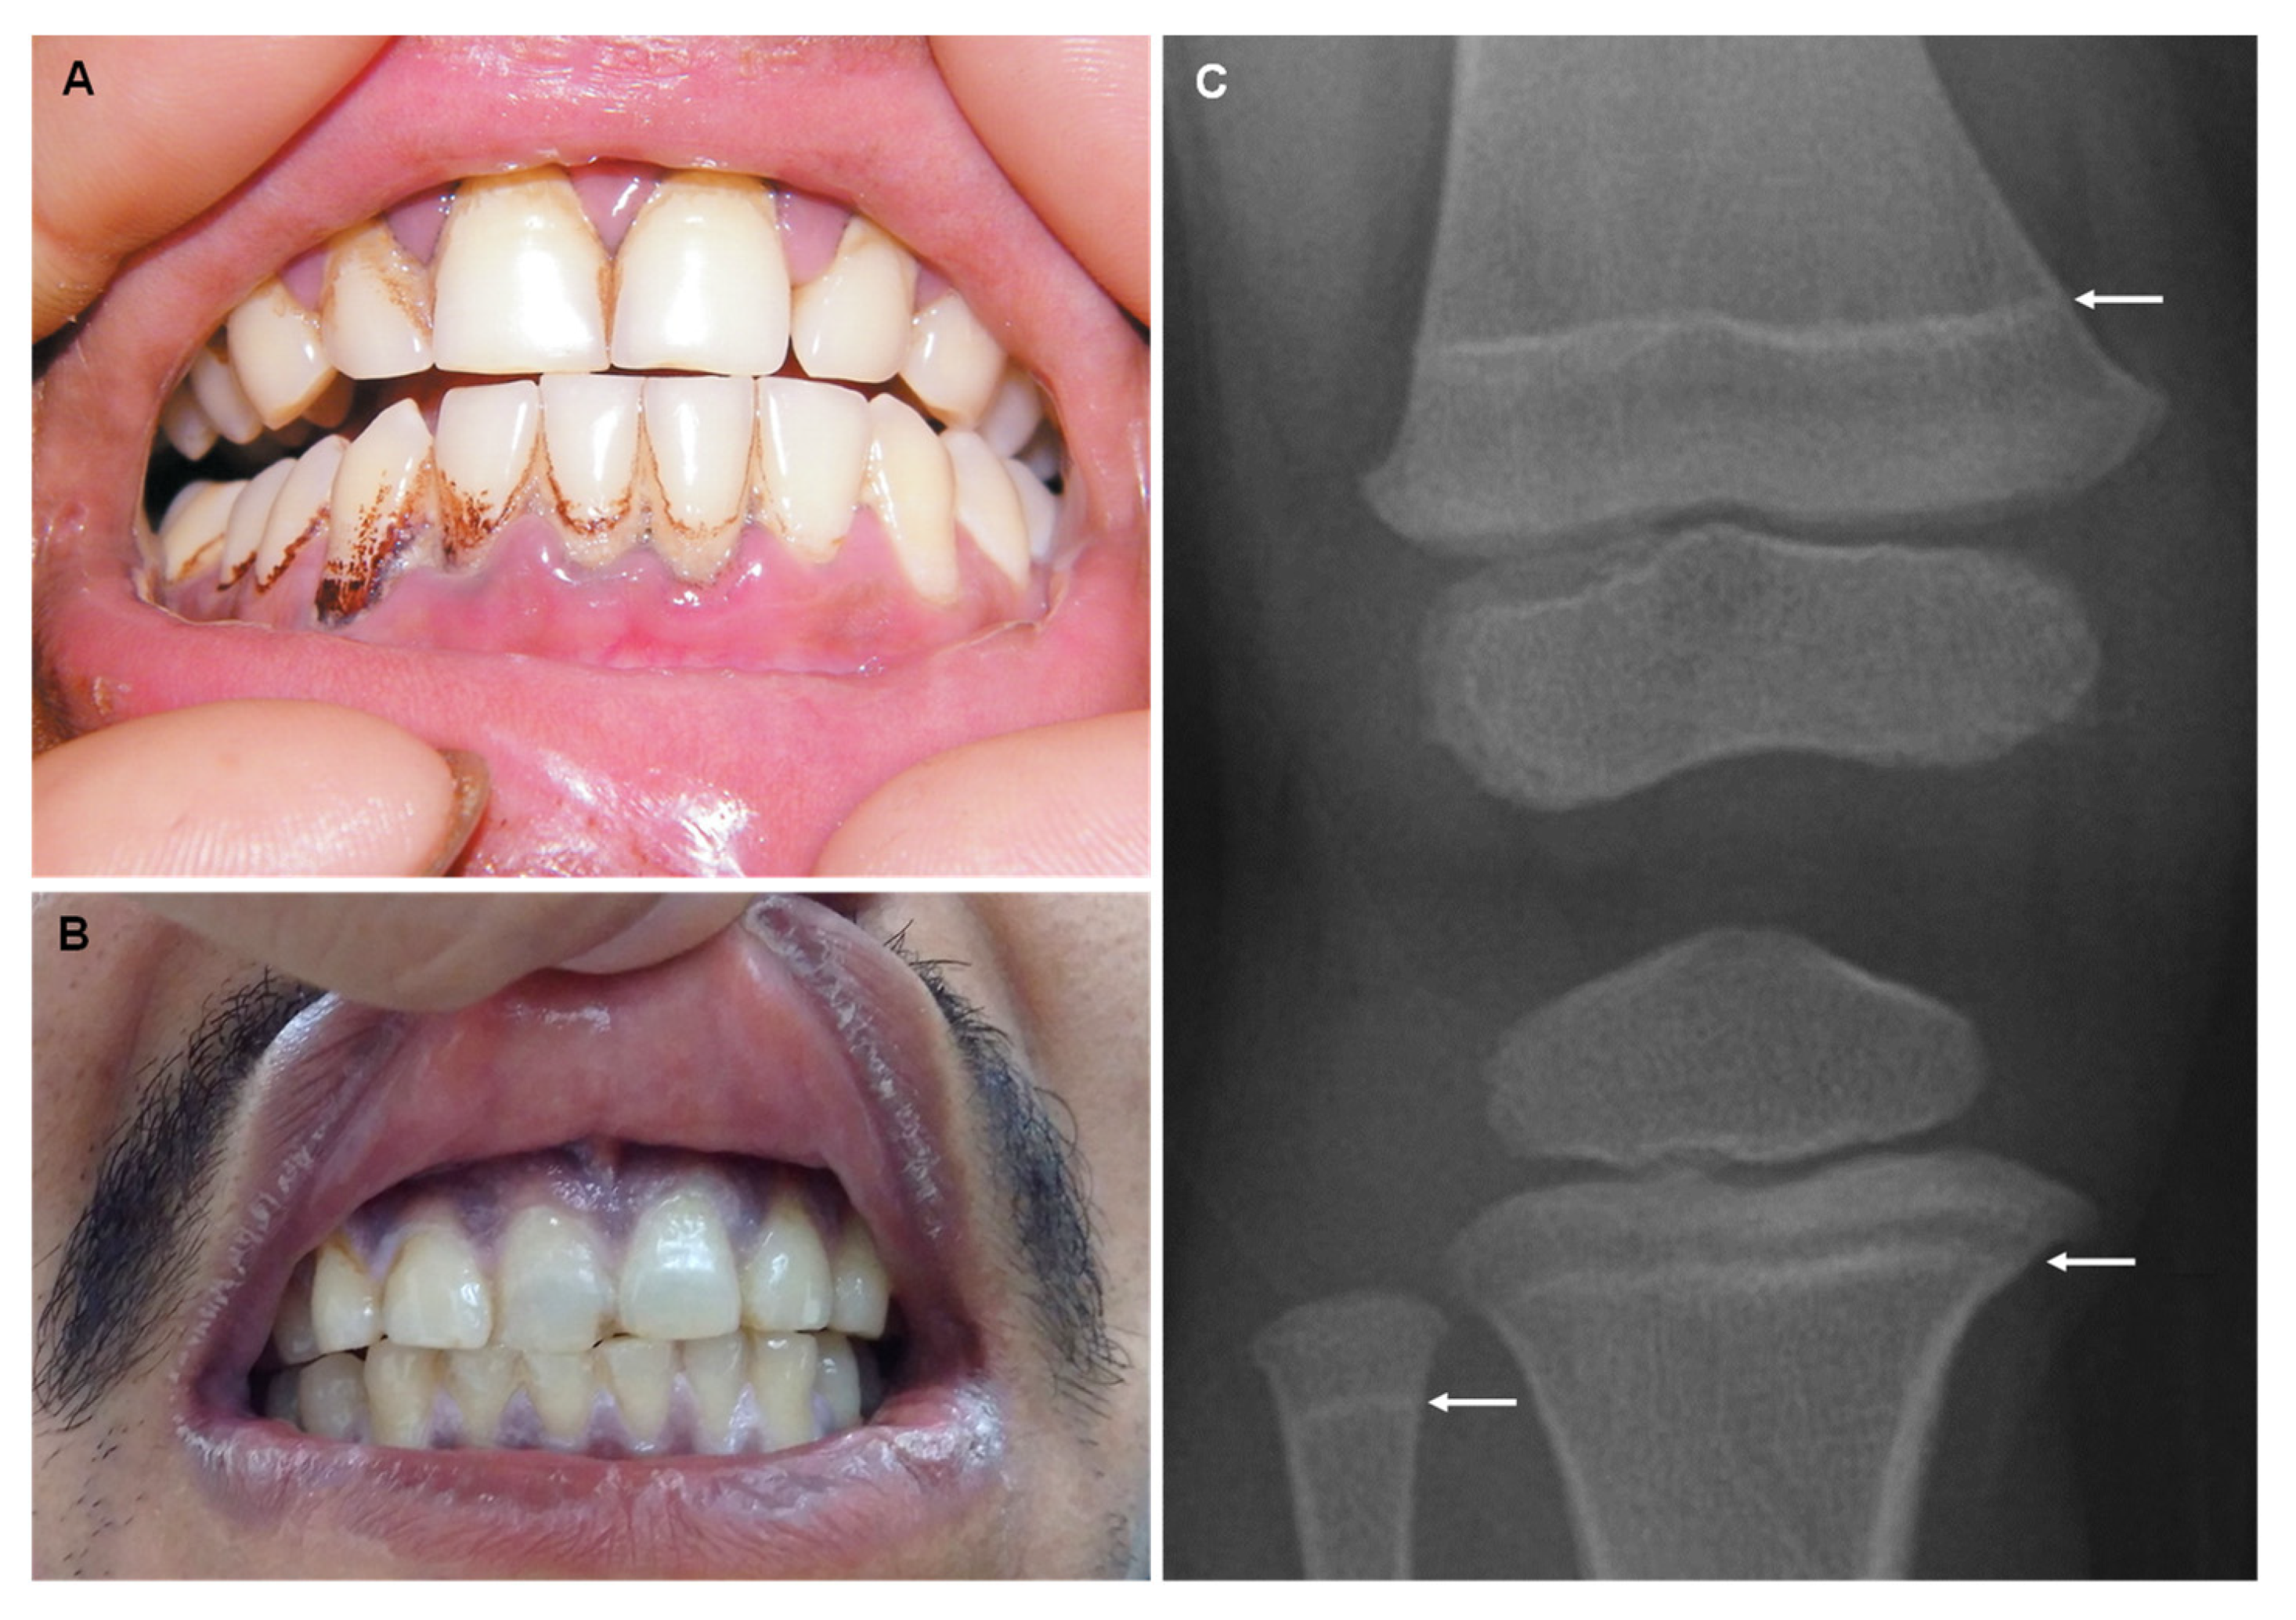

12. Bismuth

| Bismuth (Bi) |

| “Bismuth line”: bluish black gum discoloration Gingivostomatitis and ulceration Blackening of the tongue and teeth |